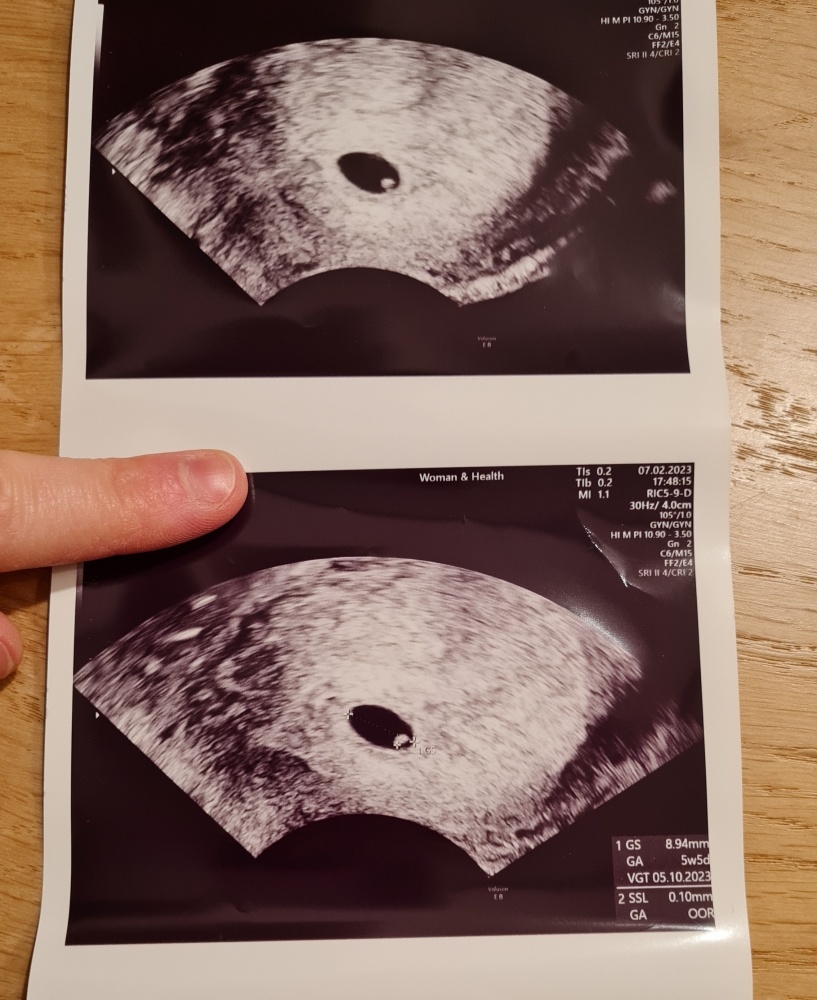

Ich bin heute bei 5+5 und war erneut bei einem Ultraschall im Vergleich zum letzten Mal hat sich alles ein wenig vergrößert allerdings bin ich wahnsinnig nervös und wende mich, wenn ich darf, wieder mit meinen Fragen an euch! Man könnte heute keinen Herzschlag sehen und das macht mich gerade so unglaublich fertig :-(

1) Was ist der weiße Punkt genau? Ist das schon "das Baby"

Zu deinen Fragen.. dass kein Herzschlag zu sehen ist, finde ich anhand meiner Erfahrungen völlig normal. Bei 5+ hat man bei mir auch nie mehr als den Dottersack gesehen. Was auch deine Frage nach dem weißen Punkt beantwortet. Der Dottersack dient zu Beginn der Schwangerschaft der Versorgung des Babys. Die Ultraschallbilder meiner Söhne sahen zu diesem Zeitpunkt genauso aus und ich war auch so zeitig beim Gyn ohne medizinischer Indikation. Meine Ärztin hat auch vor der 7. oder 8. Woche geschallt.

• Ich war im Oktober bei 5+5 das erste Mal beim Gyn. Mir war aber bewusst, dass man mit ziemlicher Sicherheit noch keinen Herzschlag sehen wird. Aber ich wollte halt trotzdem sichergehen, dass alles mal am rechten Fleck ist. Somit kann ich natürlich nachvollziehen, weshalb du bereits zweimal zum US warst ;-)

Ich lasse dir mal meine US-Bilder von 5+5 und 6+5 da. Da sieht man schön was sich da in so kurzer Zeit tut 😊2da25590-a727-11ed-9e0f-f32658c241b0.jpeg2df816b0-a727-11ed-9e0f-f32658c241b0.jpegIch bin nun schon bei der Halbzeit angelangt und alles ist okay. Dein US Bild schaut für mich für SSW 6 vollkommen in Ordnung aus. Mehr sieht man zu dem Zeitpunkt einfach noch nicht. Also versuche deinem Krümelchen zu vertrauen ☺️